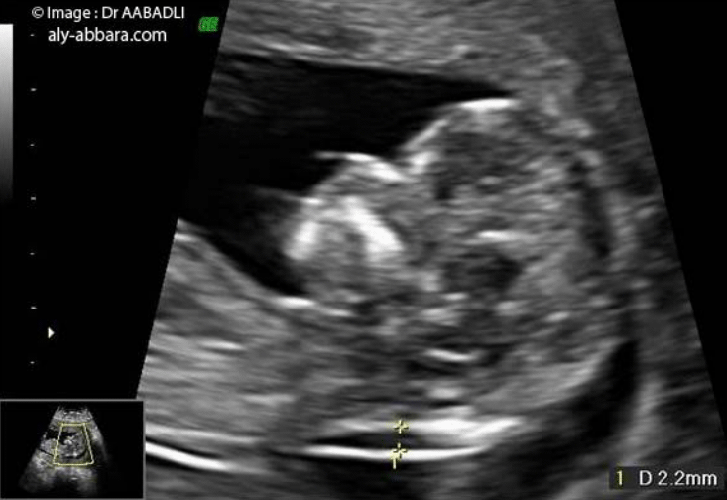

L'échographie de la clarté nucale est un test de dépistage qui permet d'évaluer le risque que votre bébé soit atteint du syndrome de Down (trisomie 21) BabyCenter Canada BabyCenter Canad ;468 Down syndrome) », Prenat Diagn, vol 30, no 1, 10, p 5764 (PMIDSpé chir et gynécoobst, s21DP 34,02 EUR Spé chir et gynécoobst, s21DP OPTAM 37,05 EUR Spé chir et gynécoobst, non conventionné 34,02 EUR Il s'agit de la choriocentèse, qui consiste à prélever un très petit fragment du placenta (villosités) Ce geste est réalisé entre 10 et 12 semaines d' aménorrhée , en cas de fort

Clarté nucale prix La clarté nucale est donc tjrs mesurée entre 35 et 39mmTout le reste est tjrs tout à fait normal Je n aurai pas de biopsie car je suis sous aspegic et qu avec mes antécédent de fc, le ratio beneficerique est pour eux important Ventriculomégalie et kystes plexus choroïdes J'ai fait l'échographie morphologique vendredi matin dernier et il en est ressorti que les ventricules cérébraux de mon papoute sont plus gros que la moyenne (moyenne ne devrait pas dépasser 10mm et moi j'en suis à 10,5mm) De plus, ils ont décelé des kystes sur les plexus choroïdesLe fœtus continue doucement sa grossesse et atteint en cette vingtetunième semaine de grossesse, la taille de 24 cm pour environ 450 grammes Faisons le point sur cette 19ème semaine d'aménorrhée 19ème semaine de grossesse pour la maman 19 SG/21SA, le ventre commence